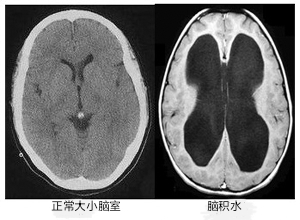

門(mén)診中,常遇到這樣的老人:走路步基寬,容易摔跤;明明記得往事,卻總丟三落四;甚至突然尿急,來(lái)不及上廁所...家人往往以為是“老了”、“帕金森”或“老年癡呆”。但有一種情況,癥狀很像,卻能被手術(shù)逆轉(zhuǎn)!它就是正常顱壓腦積水(NPH)。今天,我們就來(lái)揭開(kāi)它的“隱形面紗”。一、壓力“正?!?,為何傷腦?認(rèn)識(shí)NPH想象一下,大腦里有一套“水管系統(tǒng)”(腦脊液循環(huán)),負(fù)責(zé)滋養(yǎng)和緩沖。當(dāng)這個(gè)系統(tǒng)“堵了”,水排不出去,腦室(大腦里的“水池”)就會(huì)被撐大。關(guān)鍵點(diǎn)來(lái)了:這種堵塞造成的壓力,在常規(guī)測(cè)量時(shí)可能是“正常”的!但這股持續(xù)的壓力,卻在悄悄壓迫腦組織,導(dǎo)致神經(jīng)功能受損,引發(fā)一系列癥狀。高發(fā)人群:60歲以上老人居多,男性稍多。最大誤區(qū):常被誤診為阿爾茨海默?。ɡ夏臧V呆)或帕金森病。最大希望:NPH是少數(shù)可通過(guò)手術(shù)顯著改善甚至逆轉(zhuǎn)的“癡呆”類(lèi)型!二、揪出NPH!三個(gè)警報(bào)信號(hào)最關(guān)鍵NPH有個(gè)“經(jīng)典三件套”,如果家里老人出現(xiàn)以下任何兩個(gè)以上癥狀,務(wù)必提高警惕:1.走路不穩(wěn)像“企鵝”(最核心!):走路時(shí)兩腳分得很開(kāi),像踩在棉花上,步子很小。起步困難,轉(zhuǎn)身時(shí)特別容易搖晃、摔倒。手臂擺動(dòng)正常,不像帕金森那樣僵硬顫抖。家人觀察:是否頻繁摔跤?轉(zhuǎn)身時(shí)特別不穩(wěn)?2.記性變差,但“不太一樣”:不是完全忘記!過(guò)去的事記得清楚,但近期事情容易丟三落四。做事“卡殼”:知道要做什么(比如拿杯子喝水),但動(dòng)作反應(yīng)慢,好像“指揮不動(dòng)”手腳。注意力難集中,計(jì)劃事情變得困難(比如做飯步驟混亂)。家人觀察:是記不清剛發(fā)生的事,還是干脆忘記親人?做事是不是變“笨拙”了?3.憋不住尿,甚至尿褲子:早期可能是尿頻、尿急,總想上廁所。嚴(yán)重時(shí),會(huì)控制不住地尿濕褲子(尿失禁)。家人觀察:是否頻繁上廁所?有沒(méi)有來(lái)不及去廁所弄濕褲子的情況?別只當(dāng)是前列腺問(wèn)題或膀胱炎!提示:這三個(gè)癥狀不一定同時(shí)出現(xiàn),有時(shí)只出現(xiàn)一兩個(gè)。尤其走路不穩(wěn)是最敏感的信號(hào)!千萬(wàn)別簡(jiǎn)單歸咎于“人老了”。三、醫(yī)生如何確診NPH?三步走!如果懷疑是NPH,我們會(huì)進(jìn)行專(zhuān)業(yè)評(píng)估:1.詳細(xì)問(wèn)診:重點(diǎn)了解“三件套”癥狀的特點(diǎn)、出現(xiàn)時(shí)間和變化情況,以及是否有過(guò)腦外傷、腦出血、腦膜炎等病史。2.關(guān)鍵檢查-頭部影像(CT/MRI):這是必做項(xiàng)!我們主要看:腦室是不是變大了?(特別是側(cè)腦室前角像吹脹的氣球)。腦溝(腦表面的皺褶)有沒(méi)有明顯變寬?NPH患者腦溝相對(duì)正常或變淺,這和老年癡呆(腦溝明顯增寬、腦萎縮)完全不同!對(duì)比圖:左圖為AD患者腦溝圖,右圖為NPH患者腦溝圖,3.“放水”試驗(yàn)-腰椎穿刺:這是驗(yàn)證治療是否有效的“金鑰匙”!我們通過(guò)腰穿放出少量腦脊液(30-50ml),觀察48小時(shí)內(nèi):走路是否明顯變穩(wěn)了?反應(yīng)是否變快了?說(shuō)話(huà)、做事是否更利索了?排尿控制是否有改善?如果癥狀有顯著好轉(zhuǎn),就強(qiáng)烈提示是NPH,并且手術(shù)效果會(huì)很好!四、曙光:手術(shù)引流,重獲生活希望!一旦確診,且“放水”試驗(yàn)有效,腦脊液分流手術(shù)是首選治療方案!原理很簡(jiǎn)單:在大腦“水池”(腦室)里放一根細(xì)軟管,把多余的腦脊液引流到腹腔(或心房)吸收掉,解除腦組織的壓迫。效果令人鼓舞:約60%-70%的患者,走路不穩(wěn)明顯改善!約50%的患者,思維反應(yīng)、記性變好!高達(dá)80%的患者,尿失禁問(wèn)題得到緩解或解決!時(shí)機(jī)就是生命線(xiàn):越早手術(shù),效果越好!特別是癥狀出現(xiàn)1年內(nèi),大腦損傷還不太重時(shí)手術(shù),效果最佳。拖得越久(比如超過(guò)3年),恢復(fù)起來(lái)就越困難。五、韓教授給您的實(shí)用提醒:哪些人該警惕?年齡:60歲以上老人風(fēng)險(xiǎn)增加。病史:有過(guò)嚴(yán)重頭部外傷、腦出血(尤其是蛛網(wǎng)膜下腔出血)、腦膜炎的人,更要留心。家人自查(劃重點(diǎn)):?走路不穩(wěn),尤其轉(zhuǎn)身容易摔跤??近期記性變差(丟三落四),但過(guò)去的事記得清??憋不住尿,甚至尿褲子?如果家里長(zhǎng)輩符合≥2條,特別是走路不穩(wěn)+其中任何一條,請(qǐng)務(wù)必盡快帶TA到神經(jīng)內(nèi)科就診!千萬(wàn)別陷入這些誤區(qū):?“人老了,走路慢點(diǎn)、記性差點(diǎn)正常!”?“尿褲子?肯定是前列腺(男)/膀胱松了(女)!”?“癡呆?沒(méi)法治了,認(rèn)命吧...”結(jié)語(yǔ):正常顱壓腦積水(NPH)就像一個(gè)“偽裝者”,癥狀看似常見(jiàn),卻暗藏危機(jī)。但它更是神經(jīng)科醫(yī)生眼中的“希望之星”——因?yàn)樗强勺R(shí)別、可治療的“癡呆”!記住它的“三件套”:企鵝步、特殊健忘、憋不住尿。尤其當(dāng)走路不穩(wěn)成為“主角”時(shí),務(wù)必多留個(gè)心眼。早一天識(shí)別,早一天評(píng)估,早一天手術(shù),就可能幫老人找回穩(wěn)穩(wěn)的步伐、清晰的頭腦和生活的尊嚴(yán)!【轉(zhuǎn)發(fā)提醒家人朋友,別讓“隱形威脅”偷走長(zhǎng)輩健康!】